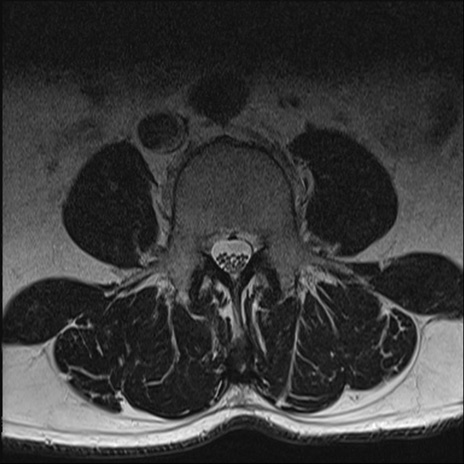

【整形】TIPS症例2 腰椎MRI T2WI(横断像)

【症例】70歳代男性

【主訴】左下肢痛

【現病歴】2週間前くらいから腰痛、左下肢痛あり。左臀部から大腿、下腿外側のしびれが常時ある。歩行とともに同部位の痛みあり。

【身体所見】Lasegue70-/60+、Bragard-/±、PTR ±/±、ATR -/-、IP 5/5、TA 5/4、TS 5/5、EHL 右第1足趾なし/3、FHL 5/5、hypersthesia(-)、足背動脈触知良好

異常所見と診断は?